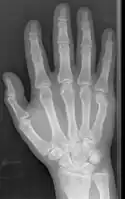

Boxer fracture -

Boxer fracture of the 4th and 5th knuckles